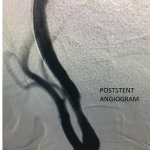

Figure 2.

Catheter angiography prior to angioplasty revealed critical stenosis (Figure 2). Angioplasty was therefore performed under local anesthesia with an embolic protection device deployed to catch any dislodged debris (Figure 3). After angioplasty, a stent was opened across the lesion to maintain long-term patency (Figure 4). Post-stent angiography showed smooth dilatation of the lesion. The patient’s aphasia continued to improve at his 6-week follow-up visit and duplex revealed no significant stenosis through the stent.